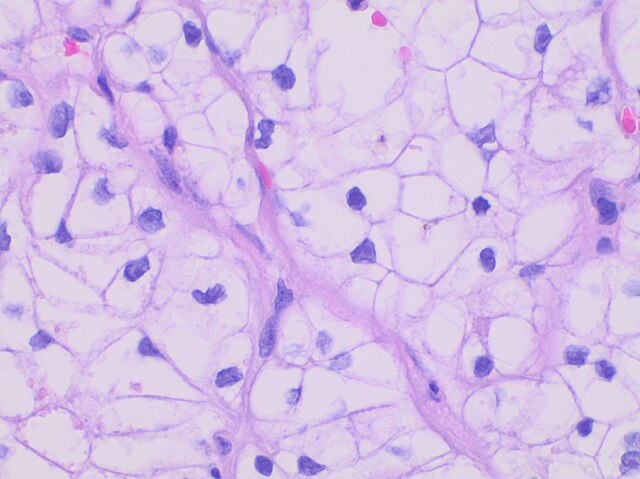

आज विज्ञान साफ कह रहा है कि हर जानवर, चाहे वह गन्ने के खेतों के पास घूमता बाघ हो या शाहजहांपुर के तालाबों में तैरता कोई छोटा पक्षी खास तरह की कोशिकाओं से बना होता है। इन कोशिकाओं के अपने-अपने काम, पहचान और बनावट होती है। वैज्ञानिक अब इन कोशिकाओं को नाम दे रहे हैं, उनकी आपस में तुलना कर रहे हैं और समय के साथ इन्हें ट्रैक भी कर रहे हैं। इसे एक तरह से 'फौना एनिमल सेल टाइप' (Fauna Animal Cell Type) कहा जा रहा है, यानी जानवरों की दुनिया में किस-किस तरह की कोशिकाएँ पाई जाती हैं, उसकी सूची और समझ।

एक समय था जब शरीर के अंगों को बस मांस के टुकड़ों की तरह देखा जाता था। धीरे-धीरे पता चला कि हर अंग लाखों-करोड़ों कोशिकाओं से मिलकर बना है, और हर कोशिका का अपना अलग काम है। यहाँ पर 'सेल ओन्टोलॉजी' (Cell Ontology) ने बड़ा बदलाव लाया। इसे आप कोशिकाओं की वैज्ञानिक 'डिक्शनरी' (dictionary) मान सकते हैं, जिसका काम यह तय करना है कि किस तरह की कोशिका को दुनिया भर की प्रयोगशालाओं में एक ही नाम और एक ही परिभाषा से पुकारा जाए।

पिछले कुछ वर्षों में जीव विज्ञान में एक और बड़ी क्रांति आई है, 'सिंगल-सेल ओमिक्स' (Single-cell omics)। पहले किसी जानवर के किसी अंग (जैसे जिगर, फेफड़े या दिमाग) को एक साथ पढ़ा जाता था, और यह मान लिया जाता था कि पूरे अंग की औसत तस्वीर ही काफी है। अब तकनीक इतनी आगे बढ़ गई है कि एक-एक कोशिका को अलग करके देखा और समझा जा सकता है। यह वैसा ही है जैसे पहले हम पूरा जंगल सिर्फ ऊपर से देखते थे, पर अब हर पेड़ की अलग पहचान, अलग कहानी हमारे सामने है।